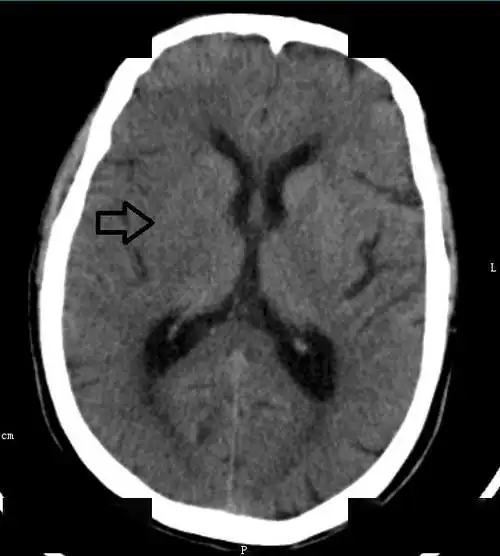

67超急性期大面积脑梗死ct平扫表现